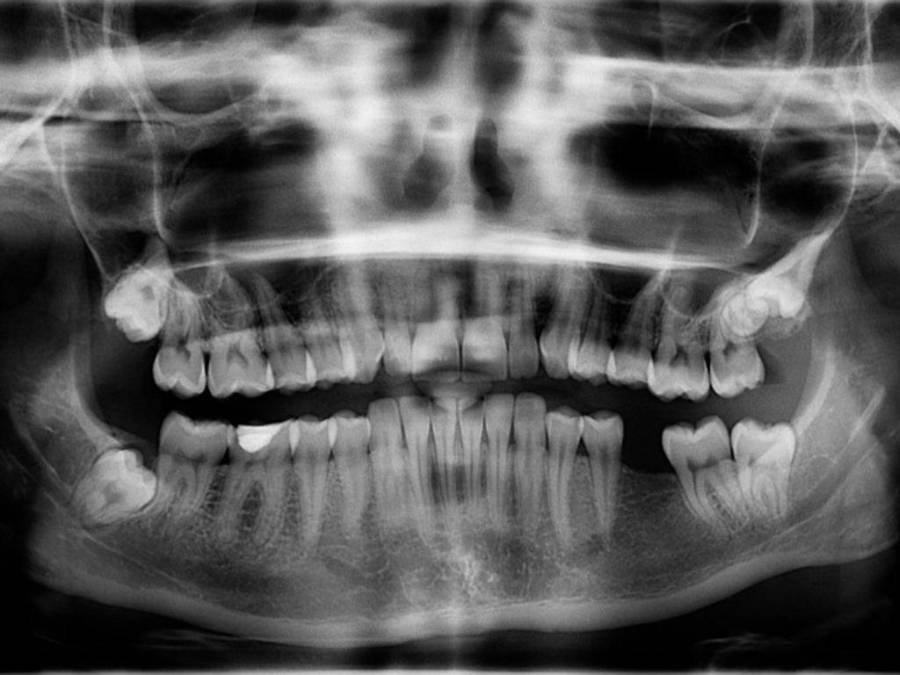

La doctora Isis Paz y otros especialista del hospital, concluyeron que la fémina fue diágnosticada con una meningitis bacteriana, es decir que presentaba bacterias que se alojaban directamente en la meninge (membrana que envuelve el encéfalo y la médula espinal).

La profesional de la medicina informó que después de realizada una tomografía cerebral, se observó una alteración vascular, a consecuencia de la misma meningitis bacteriana, por lo que fue atendida por el Departamento de Neurocirujía, pero no contaban con la maquinaria necesaria para el estudio de imágenes por lo que fue trasladada hasta el Hospital Escuela.